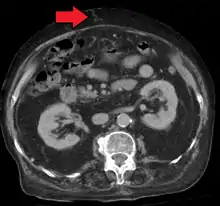

Mark.png.webp)

Ultrasonography (US) is the first-line imaging technique for the diagnosis and follow-up of portal hypertension because it is non-invasive, low-cost and can be performed on-site.[13]

A dilated portal vein (diameter of greater than 13 or 15 mm) is a sign of portal hypertension, with a sensitivity estimated at 12.5% or 40%.[14] On Doppler ultrasonography, a slow velocity of <16 cm/s in addition to dilatation in the main portal vein are diagnostic of portal hypertension.[15] Other signs of portal hypertension on ultrasound include a portal flow mean velocity of less than 12 cm/s, porto–systemic collateral veins (patent paraumbilical vein, spleno–renal collaterals and dilated left and short gastric veins), splenomegaly and signs of cirrhosis (including nodularity of the liver surface).[13]

The hepatic venous pressure gradient (HVPG) measurement has been accepted as the gold standard for assessing the severity of portal hypertension. Portal hypertension is defined as HVPG greater than or equal to 5 mm Hg and is considered to be clinically significant when HVPG exceeds 10 to 12 mm Hg.[16]